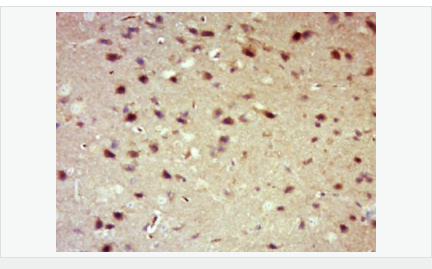

| 產(chǎn)品應(yīng)用 | WB=1:500-2000 IHC-P=1:100-500 IHC-F=1:100-500 Flow-Cyt=1μg /test. IF=1:100-500 (石蠟切片需做抗原修復(fù)) not yet tested in other applications. optimal dilutions/concentrations should be determined by the end user. |

| 產(chǎn)品介紹 | 14-3-3 are activates tyrosine and tryptophan hydroxylases in the presence of Ca (2+)/calmodulin-dependent protein kinase II, and strongly activates protein kinase C. Is probably a multifunctional regulator of the cell signaling processes mediated by both kinases. Activates the ADP-ribosyltransferase (exoS) activity of bacterial origin. 14-3-3 proteins are localized in neurons, and are axonally transported to the nerve terminals. They may be also present, at lower levels, in various other eukaryotic tissues. It belongs to the 14-3-3 family. This antibody is reactive with 14-3-3 Alpha, Beta, Gamma, Delta, Epsilon. Function: Adapter protein implicated in the regulation of a large spectrum of both general and specialized signaling pathways. Binds to a large number of partners, usually by recognition of a phosphoserine or phosphothreonine motif. Binding generally results in the modulation of the activity of the binding partner. Subunit: Interacts with CDK16 and BSPRY. Interacts with WEE1 (C-terminal). Interacts with SAMSN1. Interacts with MLF1 (phosphorylated form); the interaction retains it in the cytoplasm. Interacts with Thr-phosphorylated ITGB2. Interacts with BCL2L11. Homodimer. Heterodimerizes with YWHAE. Homo- and hetero-dimerization is inhibited by phosphorylation on Ser-58. Interacts with FOXO4, NOXA1, SSH1 and ARHGEF2. Interacts with Pseudomonas aeruginosa exoS (unphosphorylated form). Interacts with BAX; the interaction occurs in the cytoplasm. Under stress conditions, MAPK8-mediated phosphorylation releases BAX to mitochondria. Interacts with phosphorylated RAF1; the interaction is inhibited when YWHAZ is phosphorylated on Thr-232. Interacts with TP53; the interaction enhances p53 transcriptional activity. The Ser-58 phosphorylated form inhibits this interaction and p53 transcriptional activity. Interacts with ABL1 (phosphorylated form); the interaction retains ABL1 in the cytoplasm. Interacts with PKA-phosphorylated AANAT; the interaction modulates AANAT enzymatic activity by increasing affinity for arylalkylamines and acetyl-CoA and protecting the enzyme from dephosphorylation and proteasomal degradation. It may also prevent thiol-dependent inactivation. Interacts with AKT1; the interaction phosphorylates YWHAZ and modulates dimerization. Interacts with GAB2 and TLK2. Subcellular Location: Cytoplasm. Melanosome. Note=Located to stage I to stage IV melanosomes. Post-translational modifications: The delta, brain-specific form differs from the zeta form in being phosphorylated. Phosphorylation on Ser-184 by MAPK8; promotes dissociation of BAX and translocation of BAX to mitochondria. Phosphorylation on Ser-58 by PKA; disrupts homodimerization and heterodimerization with YHAE and TP53. This phosphorylation appears to be activated by sphingosine. Phosphorylation on Thr-232; inhibits binding of RAF1. Similarity: Belongs to the 14-3-3 family. SWISS: P31946 Gene ID: 7529 Database links: Entrez Gene: 7529 Human Entrez Gene: 54401 Mouse Omim: 601289 Human SwissProt: P31946 Human SwissProt: Q9CQV8 Mouse Unigene: 643544 Human Unigene: 34319 Mouse Unigene: 485025 Mouse Unigene: 8653 Rat Important Note: This product as supplied is intended for research use only, not for use in human, therapeutic or diagnostic applications. 信號傳導(Signaling Intermediates) 14-3-3蛋白是一個涉及調(diào)節(jié)細胞凋亡、促細胞分裂信號傳導和細胞周期關(guān)卡的蛋白質(zhì)家族。它被認為是通過與絲氨酸殘基磷酸化的蛋白質(zhì)的結(jié)合介導的信號傳導中的關(guān)鍵調(diào)節(jié)物。通過與Bad(相關(guān)死亡因子)的結(jié)合, 14-3-3 蛋白由于將Bad隔離于胞液而防止了細胞凋亡。 蛋白是14-3-3家族成員。它廣泛分布于哺乳動物、兩棲類、昆蟲、植物和酵母菌的真核生物高度保守性多功能蛋白質(zhì)。 目前已知至少有16個成員。此抗體識別分子量為30-31kDa的14-3-3蛋白αβγδε亞型。 |